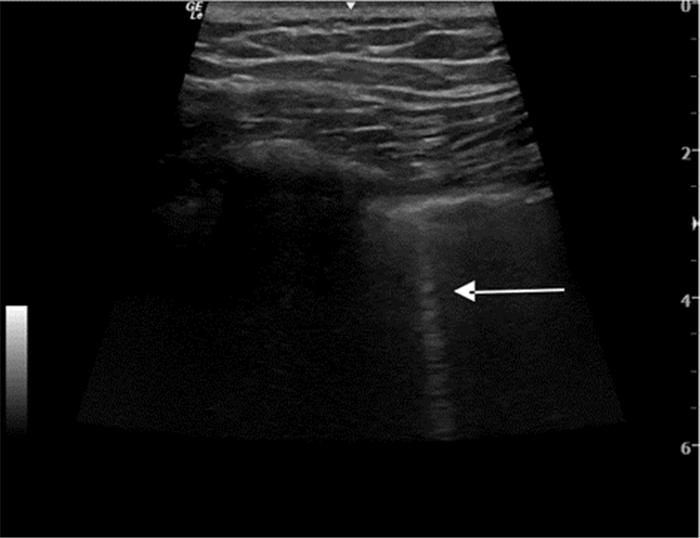

超声检查IVC内径及其随呼吸的变异率不但能提供患者容量状态的信息,有时还能评估液体反应性(图 19、20)。ASE(美国心超协会)指南的建议:用力吸气时,IVC直径≤2.1 cm伴随呼吸变异率>50%,对应于中心静脉压(CVP)值3 mmHg(0~5 mmHg,1 mmHg=0.133 kPa),IVC直径>2.1 cm伴随呼吸变异率<50%,对应的CVP值为15 mmHg(10~20 mmHg);如IVC直径≤2.1 cm伴随呼吸变异率<50%或IVC直径>2.1 cm伴随呼吸变异率>50%,提示对应的CVP值可能为8 mmHg(5~10 mmHg),此时应考虑采用其他指标来估测CVP[1]。其他文献报道数值略有不同,平静呼吸时,IVC直径≤2 cm伴随呼吸变异率>50%,对应于CVP值≤10 mmHg,可见于低血容量和分布性休克患者;IVC直径>2 cm伴随呼吸变异率<50%,对应的CVP值大于10 mmHg,可见于心源性和梗阻性休克患者[2]。

| 图 19 IVC长轴切面 |

但IVC的超声成像有时比较困难,特别是肥胖、腹胀和肠胀气明显的患者;而且IVC大小还受机械通气患者呼气末正压(PEEP)的影响,用来估计CVP有一定的缺陷[3]。在完全控制通气模式下(无自主呼吸触发)时,吸气相IVC扩张超过12%~18%,可较好的预测容量反应性。IVC管径随着PEEP水平的增加而升高,呼吸变异率随PEEP的增加而变小,但目前PEEP对IVC容量评估的影响尚无定论,有待进一步临床研究。